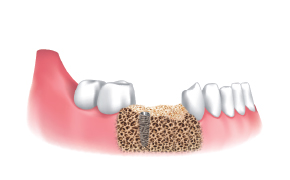

Disassemble the Silicone Shield, the Stopper and collect the bone chips for bone grafting.

Use Final Drill (equal to or over Ø3.5/4.0) according to the drilling protocol of the manufacturer and treatment planning.

Place the implant.

Apply the harvested bone chips on the site.